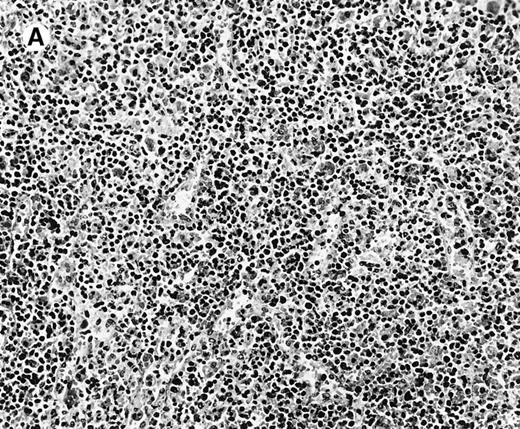

Histologic findings in the liver.

(A) Liver specimen from case 1 shows prominent portal and sinusoidal lymphoid infiltrate (hematoxylin and eosin, × 200). (B) The infiltrating lymphocytes are small and lack cytologic atypia (hematoxylin and eosin, × 600).

The immunophenotypic features and molecular data are summarized in Table 2. Immunophenotyping was performed on the spleen or liver or both in all cases. The infiltrate in all cases was composed predominantly of CD3+ T cells (Figure3A). CD20 stained attenuated residual B-cell areas in the spleen and only rare scattered B cells were identified within the liver (Figure 3B). Staining for CD4 and CD8 showed that the infiltrate was CD8+ in 2 cases (Figure4A), CD4+ in 2 cases (Figure5A), and in the remaining 2 cases CD4+ and CD8+ cells were noted in approximately equal numbers without clear subset predominance. CD4 highlighted the erythrophagocytic histiocytes (Figure 4B). The lymphocytes in all cases expressed βF1 and TIA-1+ (Figure 4C and D) and were CD56−.